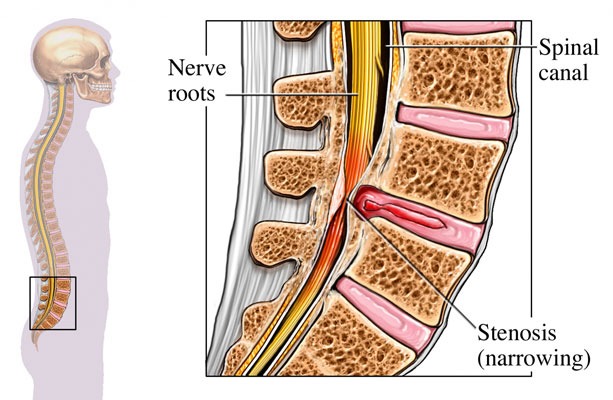

Spinal Canal Stenosis

It is the compression of the spinal cord or nerve roots due to narrowing of the spinal canal. When spinal cord injury develops, it is called myelopathy; when the damage becomes visible on MRI, it is termed myelomalacia.